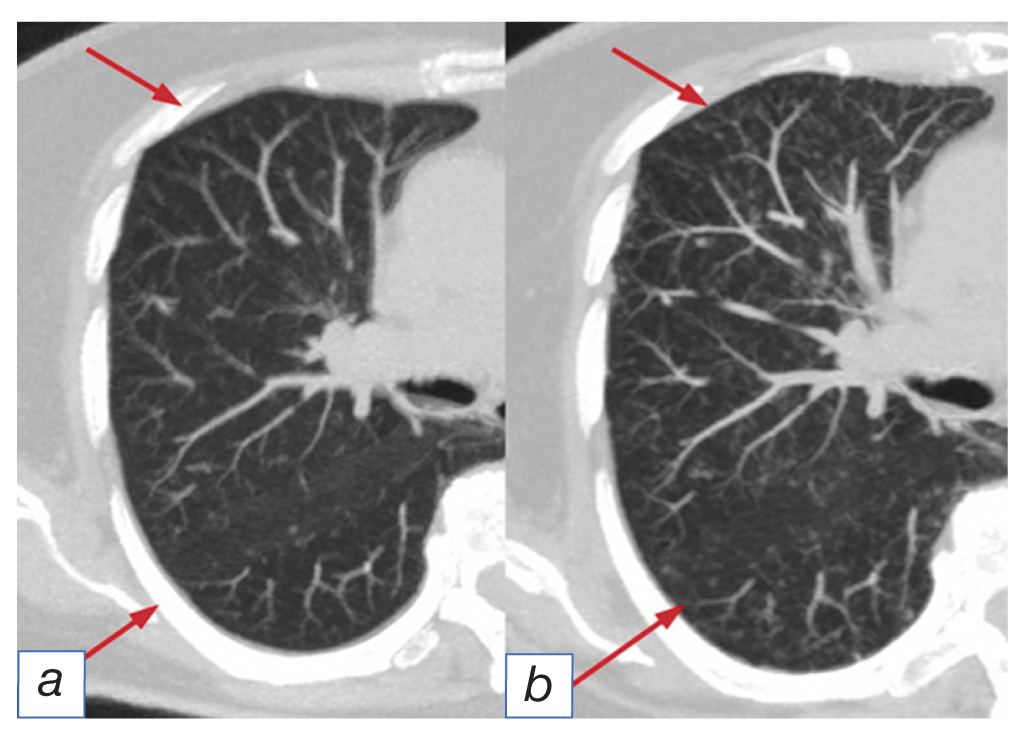

- the pattern of non-specific interstitial pneumonia [10] visualized as confluent bilateral opacity (ground glass-type) and reticular changes predominantly in the peripheral and lower areas of the lungs in the lower lobes with pronounced traction bronchiectasеs and loss of the lower lobe volume. Other findings may include peribronchovascular distribution with preserved normal pulmonary tissue subpleurally (Fig. 2);

Fig. 2. The pattern of non-specific interstitial pneumonia: before (а) and after (b) immunotherapy (arrows).